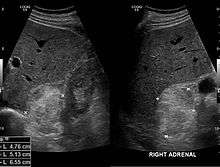

Most myelolipomas are unexpected findings on CT scans and MRI scans of the abdomen. They may sometimes be seen on a plain X-ray films.[6]

- 1 2 3 4 Ramchandani, P. Adrenal Myelolipoma Imaging at eMedicine